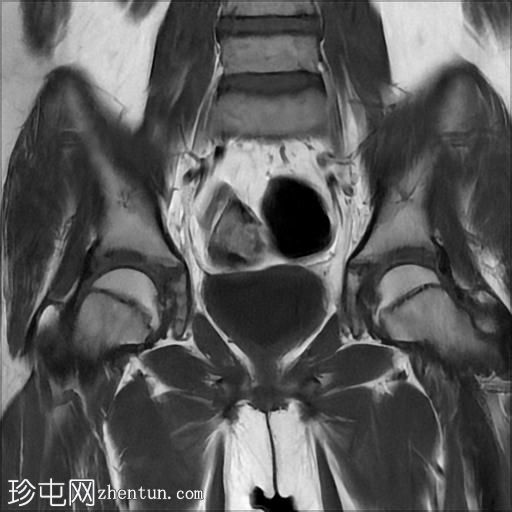

冠状面T2

脂肪饱和度

MRI序列显示:

女性外生殖器

子宫、宫颈及阴道上2/3缺失

左侧睾丸及腹股沟管内环

右侧睾丸位于腹腔内,靠近腰大肌

双侧卵巢未显影

MRI结果提示雄激素不敏感综合征 (AIS),患者基因构成为男性,但外生殖器为女性(46XY核型)。由于细胞对睾酮等雄激素产生抵抗,雄激素不敏感综合征常伴有双侧隐睾。

区分雄激素不敏感综合征与Mayer-Rokitansky-Küster-Hauser综合征(MRKH)至关重要。MRKH综合征具有女性核型,女性外生殖器和卵巢正常,但子宫缺失或发育不全。